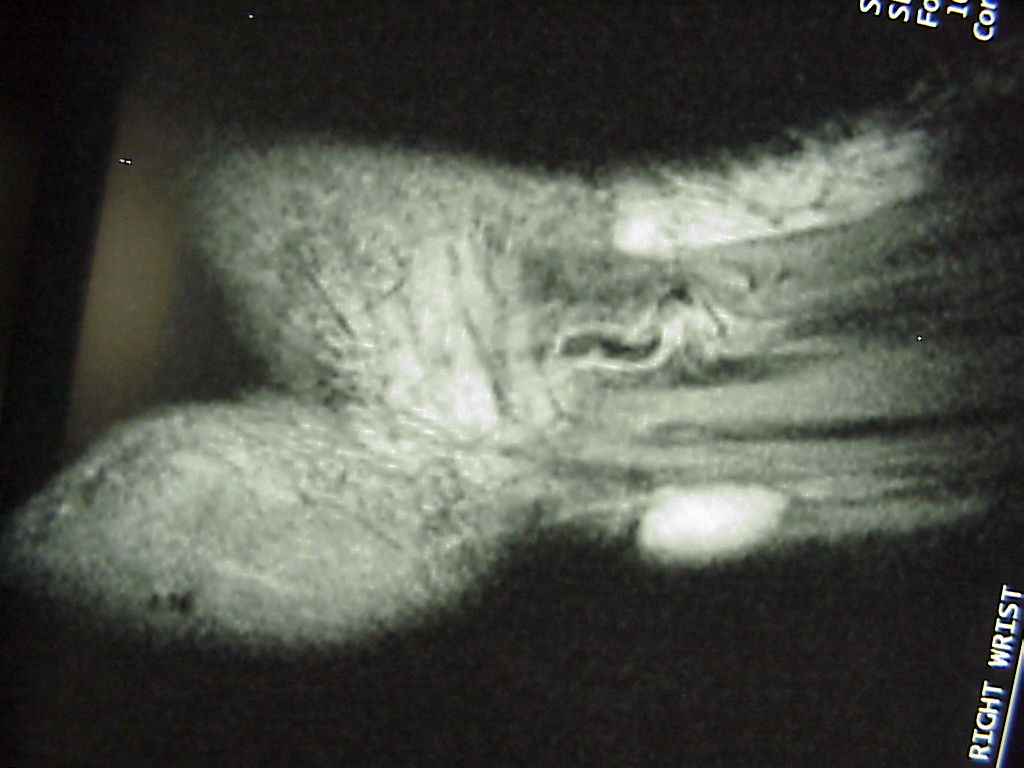

Clinical Example: Volar wrist ganglions

volar wrist ganglion